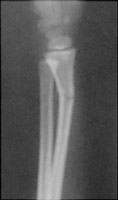

The greenstick fracture results from direct trauma. There is an incomplete fracture of a long bone (radius or ulna) with cortical disruption on one side and deformity on the other, resulting in bowing of the bone.

- Click on the image for a larger versionAAP radiograph of the forearm. This demonstrates the typical appearance of a greenstick fracture.